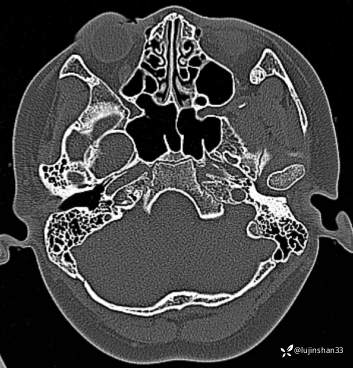

【主诉】:检查发现右侧颅中窝肿物3月

【现病史及既往史】:患者3月前头部磕碰后感疼痛,当时被老师送到XX市XX县人民医院,行CT检查提示颅内肿物,又继续到XX省第二人民医院行头颅核磁示:右侧颅中窝肿物,建议手术治疗,于7月23日入住我科拟行手术,但患儿极度不配合,办理出院回家调整,现完善心理建设,要求手术。

【临床诊断】:颅底占位